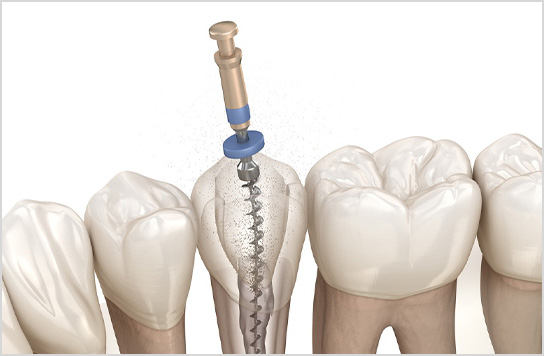

患者さんのニーズが高い顕微鏡歯科治療のご紹介

神奈川県川崎市中原区/武蔵小杉駅1分の歯医者です。根管治療や歯髄温存、歯周病、破折歯など、歯を残す治療を専門に行っています。患者さんから評価の高い、マイクロスコープ活用の歯科治療をご紹介。

他院で抜髄(歯の神経を取る)

と言われたケースでも

団髄法やMTA活用で可能な

限り神経を残します。

■根管治療

歯の根に膿がたまり他院で抜歯宣告をされた歯。最終的に抜歯せずに治療ができたケース。

過去の根管治療が再発し再感染したケース。当院で再根管治療を実施し、歯を残した。